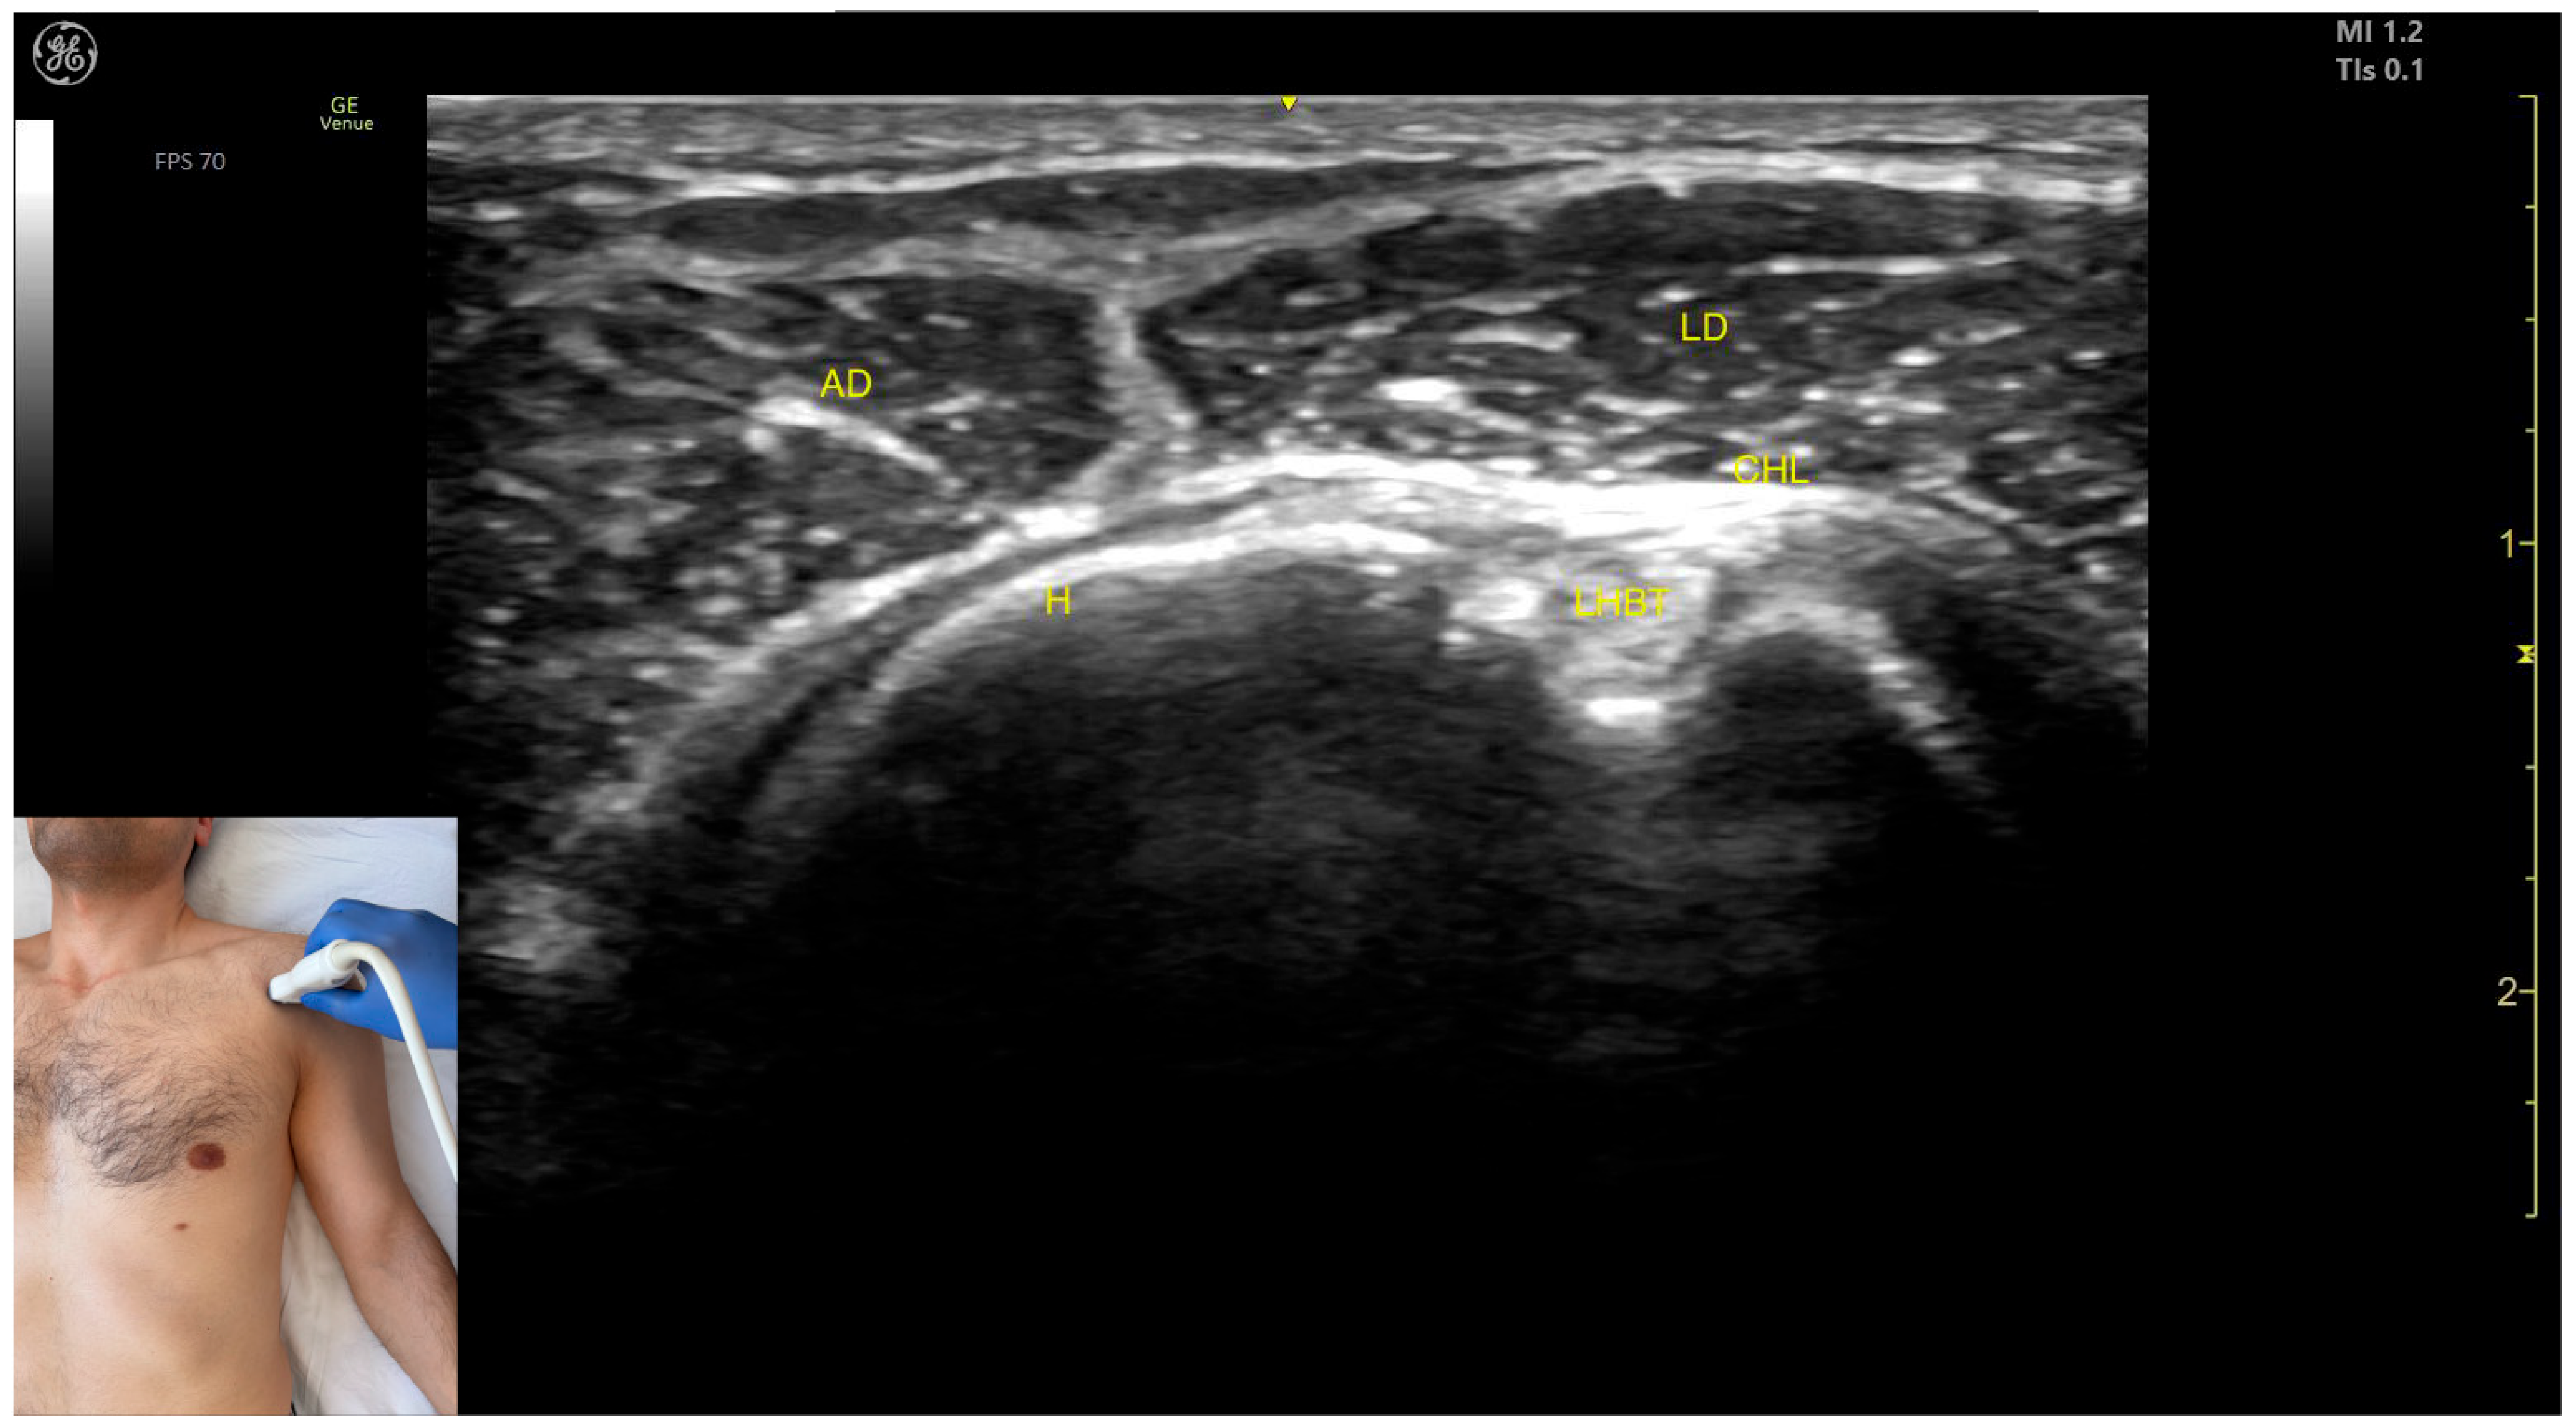

Ultrasound Identification

Key Ultrasound Landmarks

- Muscle position: It represents a superficial muscle mass on the anterior surface of the proximal arm. Deep to the anterior deltoid, the LHBT is located in the bicipital groove of the humerus, encased in the superficial portion of the coracohumeral ligament (CHL). Superficial to the LHBT, the lateral deltoid is observed, with the AD positioned anterior to the lateral deltoid.

- External fascia: The AD has a pronounced fascia that separates it from the subscapularis tendon, the lateral deltoid, the clavicular head of the pectoralis major, and the subcutaneous muscular plane during BoNT-A injections.

- Dynamic evaluation: During dynamic evaluation, scanning distally toward the elbow joint shows a decrease in the muscle size of the deltoid, coinciding with an increase in the muscle size of the biceps brachii. Scanning proximally toward the clavicle reveals the origin of the AD on the clavicle, along with the appearance and increased size of the clavicular head of the Pmaj [41]. Contraction of the anterior deltoid is seen during flexion and medial rotation maneuvers of the arm at the shoulder joint [12,39].